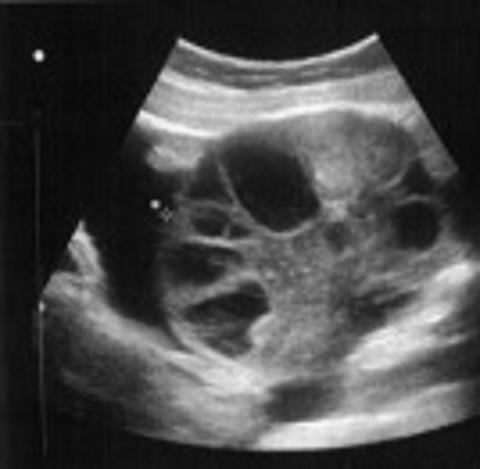

Højre ovarie fem dage efter oocytaspiration, der ses begyndende ascitesdannelse (ovariet måler 94 × 78 mm).

OHSS opdeles i flere grader efter tiden for symptomernes opståen [7] og sværhedsgraden [8]: 1) Tidlig: < 10 dage efter ægudtagning. Tilstanden skyldes det eksogent givne hCG, oftest ses et mildt og selvlimiterende forløb. 2) Sen: ≥ 10 dage efter ægudtagning. Tilstanden ses oftest ved graviditet som følge af stigende endogent produceret hCG. Sværere og længerevarende forløb ses ved både normal singletongraviditet og flerfoldsgraviditet. 3) Mild: Tilstanden ses relativt ofte ved in vitro-fertilisering (IVF) i form af forstørrede ovarier (< 8 cm) og alment abdominalt ubehag. 4) Moderat: Der ses ascitesdannelse, kvalme, opkastning, abdominale smerter, diarré og vægtøgning (> 1 kg/dag). Ovariestørrelse 8-12 cm. 5) Svær: Hæmokoncentration > 45%, hypovolæmi, væskeophobning intraperitonealt, i pleura og perikardiet. Begyndende multiorganpåvirkning, ovarier > 12 cm i diameter. 6) Kritisk: Hæmokoncentration > 55%, leukocytose > 25 × 10-9/l, multiorgansvigt (oligo/anuri, akut respiratorisk distress-syndrom, leverpåvirkning, blødning fra ovarierne, tromboemboli og dissemineret intravaskulær koagulation).